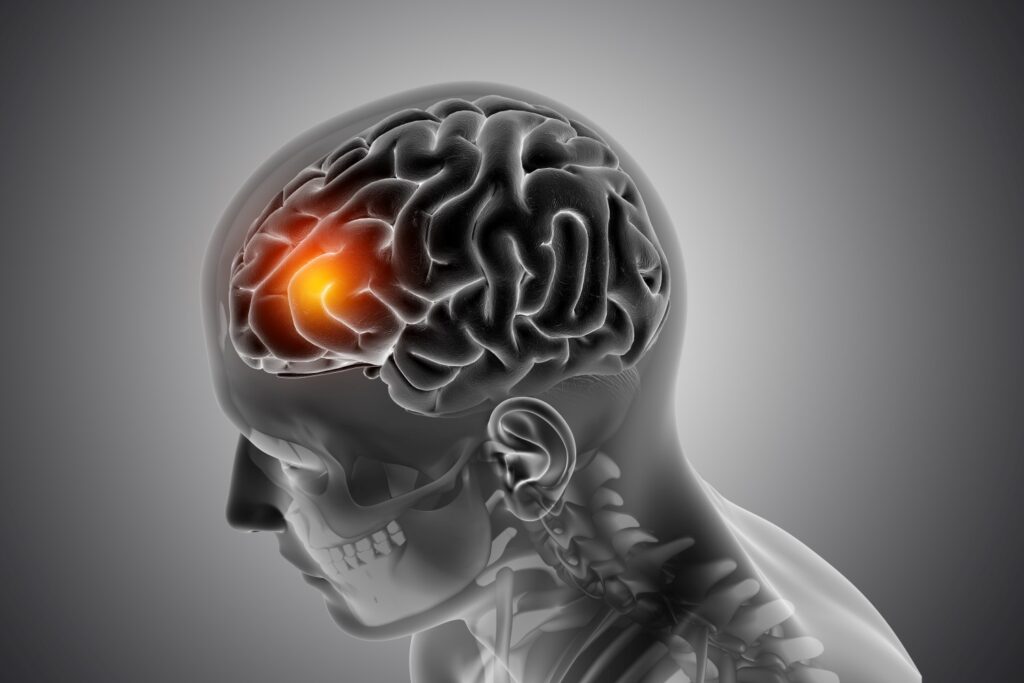

Pediatric brain tumors are abnormal cell masses that can grow in any part of a child’s brain. There are different types of brain tumors, and they can be non-cancerous (benign) or cancerous (malignant).

Some pediatric brain tumors can cause long-term impairment of intellectual and neurological function. Brain tumors in children and infants are very different from adult brain tumors.

Brain tumors are the most common cause of cancer in children.